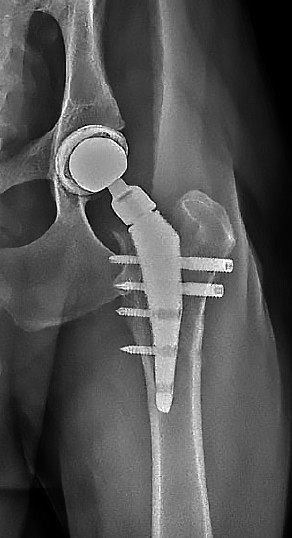

Разработан алгоритм фиксации бедренного компонента, обеспечивающий его первичную остеоинтеграцию, заключающийся в строгой последовательности проведения бикортикальных и монокортикальных винтов. Энергодисперсионная рентгеновская спектроскопия подтвердила высокую степень интеграции костной ткани в ячеистых зонах импланта, которые занимают основную часть эндопротеза. Это свидетельствует о надежном связывании ножки протеза с костным ложем уже на 45‑е сутки после установки, что является ключевым фактором долгосрочной стабильности импланта (рис. 9). Использование двух бикортикальных винтов и модификация последовательности их установки помогли минимизировать нестабильность ножки в послеоперационном периоде. Уменьшение количества винтов позволило снизить общую стоимость операции и сократить объем хирургического доступа, необходимого для их установки (рис. 8).

Рис. 9. Остеинтеграция ножки и прилегание к медиальному кортикальному слою бедренной кости на 60‑е сутки после операции (пациент из рис. 8)

Источник: составлено А.М. Пантюлиным, И.Ф. Вилковыским.

Fig. 9. Osseointegration of the stem and attachment to the medial cortex of the femur on the 60th day after surgery (patient from Fig. 8)

Source: compiled by A.M. Pantyulin, I.F. Vilkoviskiy.

В результате изменения порядка и типа винтов при тотальном эндопротезировании тазобедренного сустава у собак с использованием российской системы V@art, частота осложнений, связанных с асептической нестабильностью, снизилась, этот показатель составил менее 1 % среди 227 прооперированных животных.